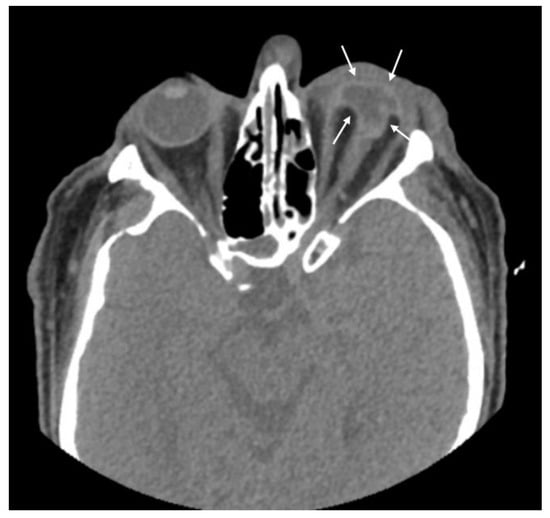

| Globe wall irregularity | 16 (53.3) |

| Asymmetric anterior chamber depth | 16 (53.3) |

| Chorioretinal layer thickening | 5 (16.7) |

| Abnormal vitreous density | 5 (16.7) |